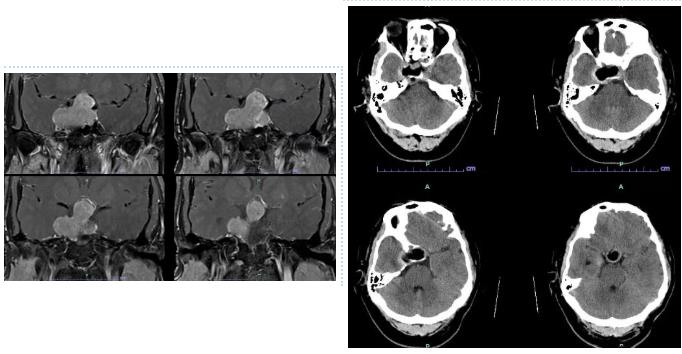

经系统检查,医生发现这并非普通代谢疾病,而是脑中一颗直径约4厘米的垂体瘤在作祟。更关键的是,这是一种生长激素型垂体瘤,肿瘤持续过量分泌生长激素,导致了患者均出现手足增大、面容改变以及继发性糖尿病和高血压,压迫视交叉,视力减退。

术后,患者当天即感精神状态好转,没有明显头痛不适,并能在床上轻微活动。术后48小时复查显示,其生长激素水平已从术前的异常高位迅速降至正常范围(1.52ng/ml)。